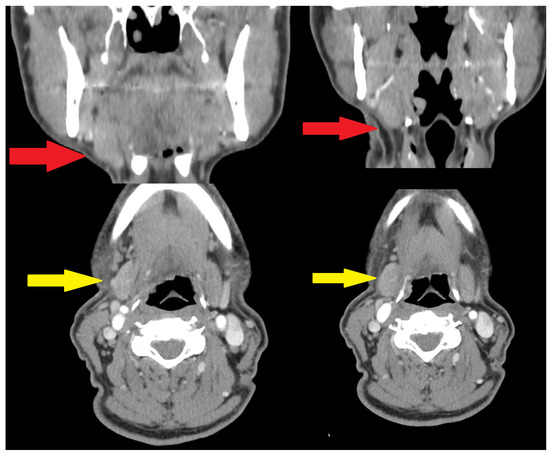

It is with great pleasure that I invite you to submit articles for the “Interesting images” Special Collection. Since we introduced Interesting Images as an article type in Diagnostics, it has served as a valuable resource for the imaging community. Many have relayed that they use these image-based case reports when encountering challenging cases or images of diseases rarely seen. Further, pitfalls are covered by this type of article and may be helpful both for experienced and less experienced image readers in making a correct evaluation.

The interesting Images together serve as a live imaging atlas covering PET, CT, MRI, and other imaging modalities. Therefore, the more cases we publish, the more likely it is that image interpreters with a difficult case can be supported by previously published cases. Although focus until now has largely been on clinical cases, it should be noted that nonclinical cases are also welcome, e.g., from preclinical in vivo imaging, including optical imaging as well as histology images from pathology.